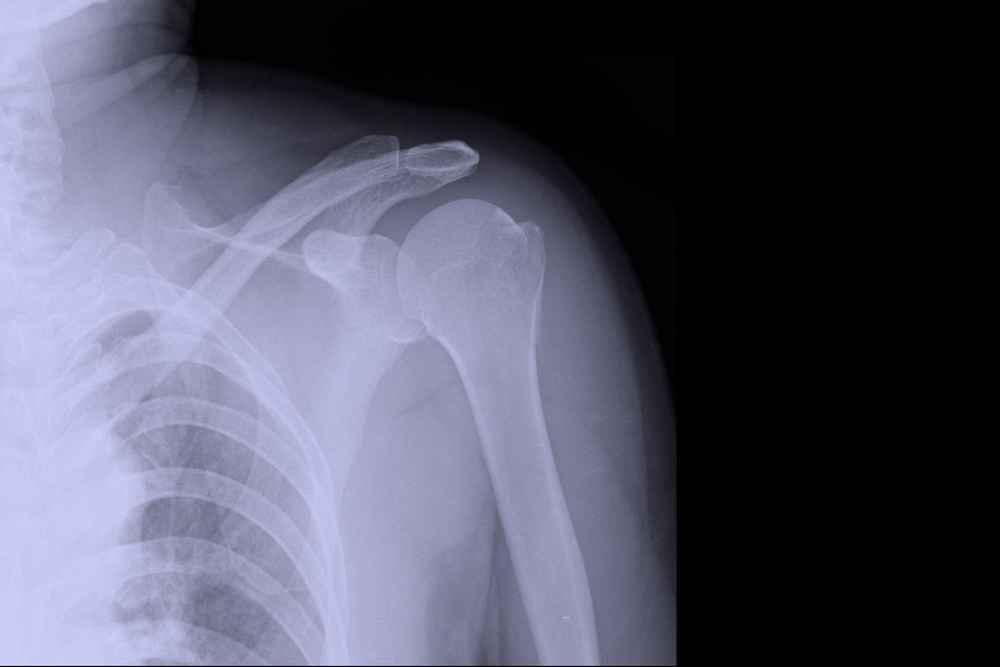

1. Sendi bahu (glenohumeral joint)

Sendi ini terbentuk antara kepala humerus (tulang lengan atas) yang berbentuk bulat dan rongga glenoid pada skapula (tulang belikat).

Struktur ini memungkinkan gerakan lengan dalam berbagai arah, termasuk fleksi, ekstensi, abduksi, adduksi, dan rotasi.